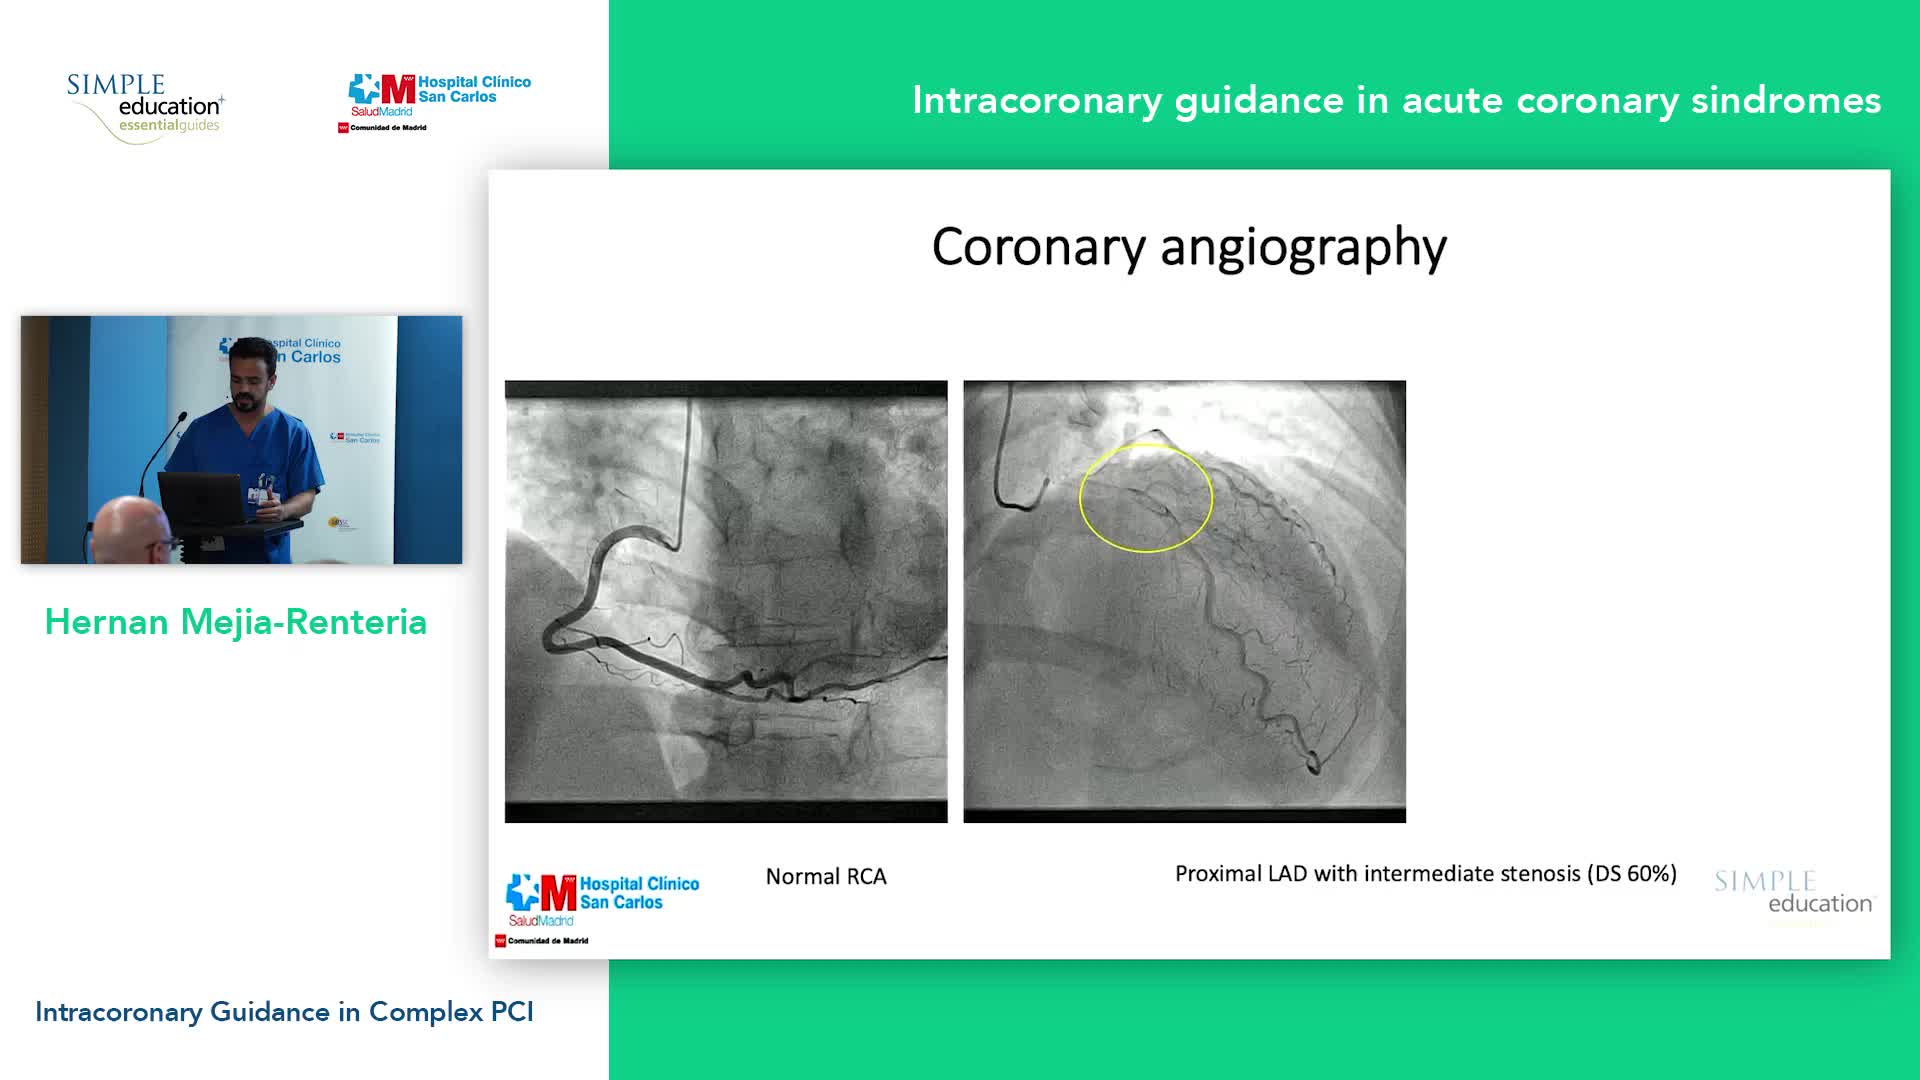

Intracoronary guidance in acute coronary syndromes - Dr Hernan Mejia-Renteria